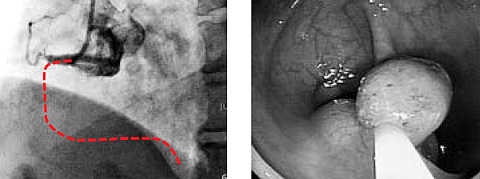

심혈관질환과 대장용종은 기름진 식사·흡연·음주 등 위험 요인을 공유한다. 혈액이 흘러야 할 심장동맥(점선 부분)이 막힌 환자의 관상동맥조영술 사진(왼쪽)과 대장용종이 발견된 대장내시경 사진(오른쪽). /한림대춘천성심병원 제공

이미지